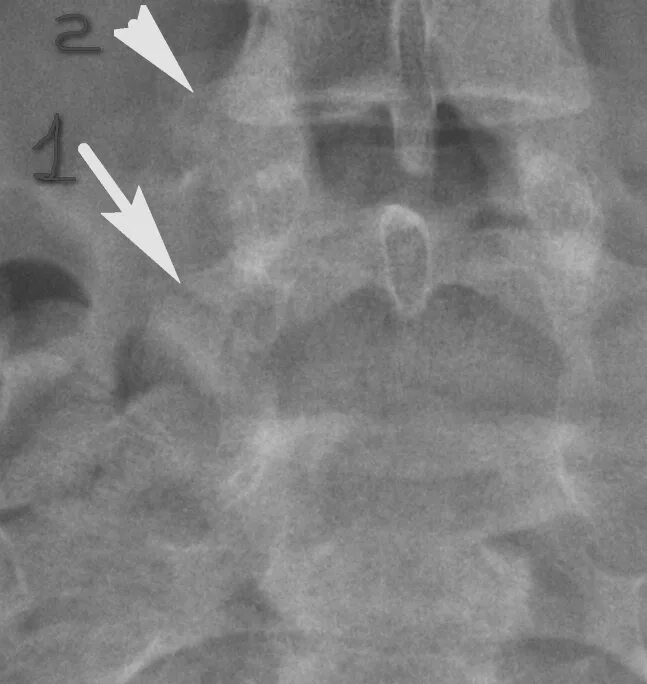

Незаращение дужки позвонка